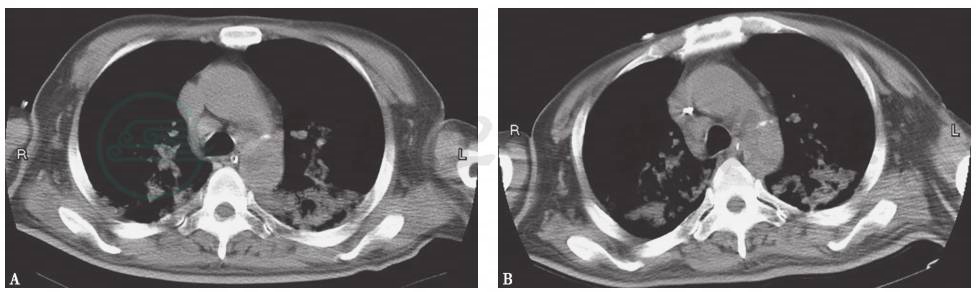

图6 吸入性肺炎胸部影像学表现

X线胸片(A)及胸部CT(B)可见双下肺渗出性病变